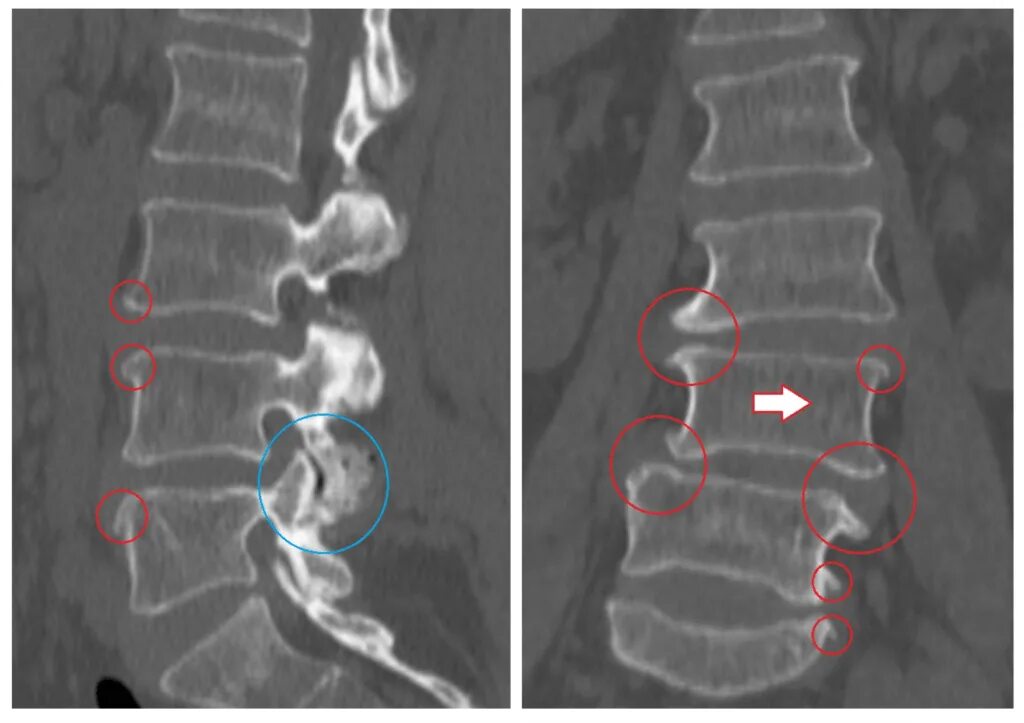

Деформирующий спондилез спондилоартроз